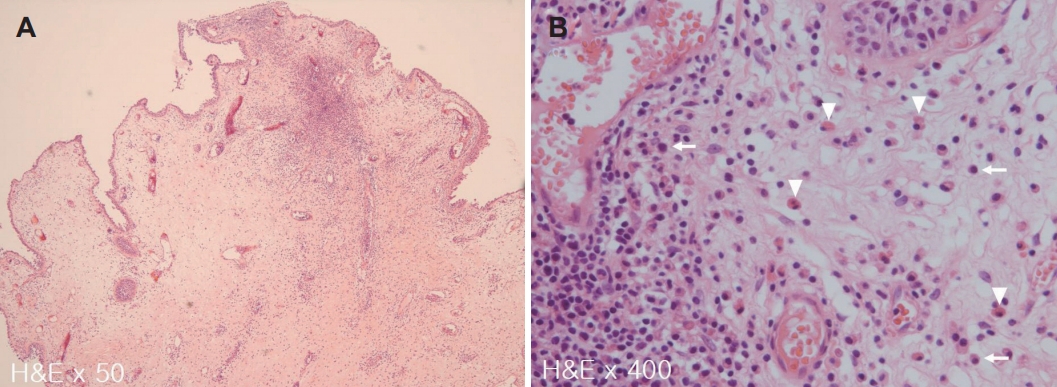

종물의 완전한 절제를 위하여 전신마취 후 비내시경을 이용한 종물 절제술(endoscopic mass excision)을 시행하기로 계획하였다. 하비갑개로 인해 종물의 기시부를 확인하는 데 제한이 있어, 하비갑개의 후방부 일부분을 절제하였다. 종물은 하비갑개의 후하방에서 기원하는 것을 확인하였고(Fig. 4), sickle knife와 cutting forceps을 가지고 주변 점막을 포함하여 완전 절제를 시행 후 재발 방지를 위해 종물의 기시부에 전기 소작을 시행하고 수술을 종료하였다. 종물의 크기는 2.0×0.8 cm이었으며 조직 병리 검사 결과는 점막하층의 부종과 호산구 및 형질세포의 침윤이 관찰되는 염증성 비용으로 최종 진단되었다(Fig. 5).

조직병리학적으로 후비공 비용과 다른 비용의 차이를 감별하기 위한 연구가 있었지만, 후비공 비용의 조직병리학적 소견은 일반적인 비용과 구분되지는 않았으며[4,9,11] 점막하 조직의 부종에 동반된 다양한 염증세포의 침윤을 보였다[1,10,12]. Min 등[13]의 연구에서 알레르기 비용과 비교하였을 때 상악동 후비공 비용의 조직에서는 점액선이 적게 분포하고 호산구 침윤이 적은 조직소견을 보인 반면, Cook 등[11]의 연구에서는 상악동 후비공 비용 조직에서 점액선 증가와 함께 호산구 및 형질세포가 증가한 소견을 보였고, 이는 본 증례와 유사한 소견을 보였다.